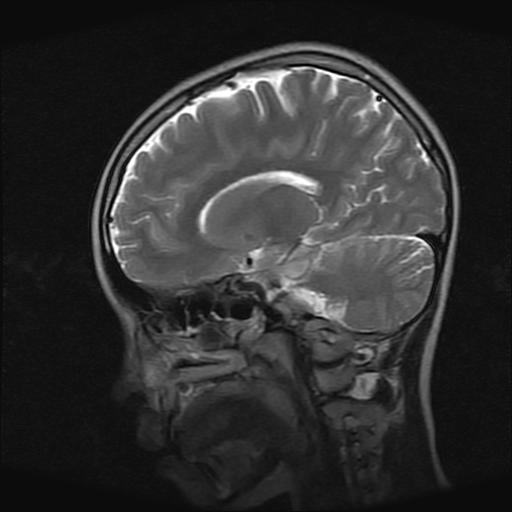

9岁女孩,三岁时诊断为癫痫,一直服丙戊酸钠,现患者一般情况良好,家长复查核磁片,看能否停药..

巨脑回